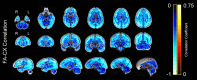

Aging is associated with widespread alterations in cerebral white matter (WM). Most prior studies of age differences in WM have used diffusion tensor imaging (DTI), but typical DTI metrics (e.g., fractional anisotropy; FA) can reflect multiple neurobiological features, making interpretation challenging. Here, we used fixel-based analysis (FBA) to investigate age-related WM differences observed using DTI in a sample of 45 older and 25 younger healthy adults. Age-related FA differences were widespread but were strongly associated with differences in multi-fiber complexity (CX), suggesting that they reflected differences in crossing fibers in addition to structural differences in individual fiber segments. FBA also revealed a frontolimbic locus of age-related effects and provided insights into distinct microstructural changes underlying them. Specifically, age differences in fiber density were prominent in fornix, bilateral anterior internal capsule, forceps minor, body of the corpus callosum, and corticospinal tract, while age differences in fiber cross section were largest in cingulum bundle and forceps minor. These results provide novel insights into specific structural differences underlying major WM differences associated with aging.